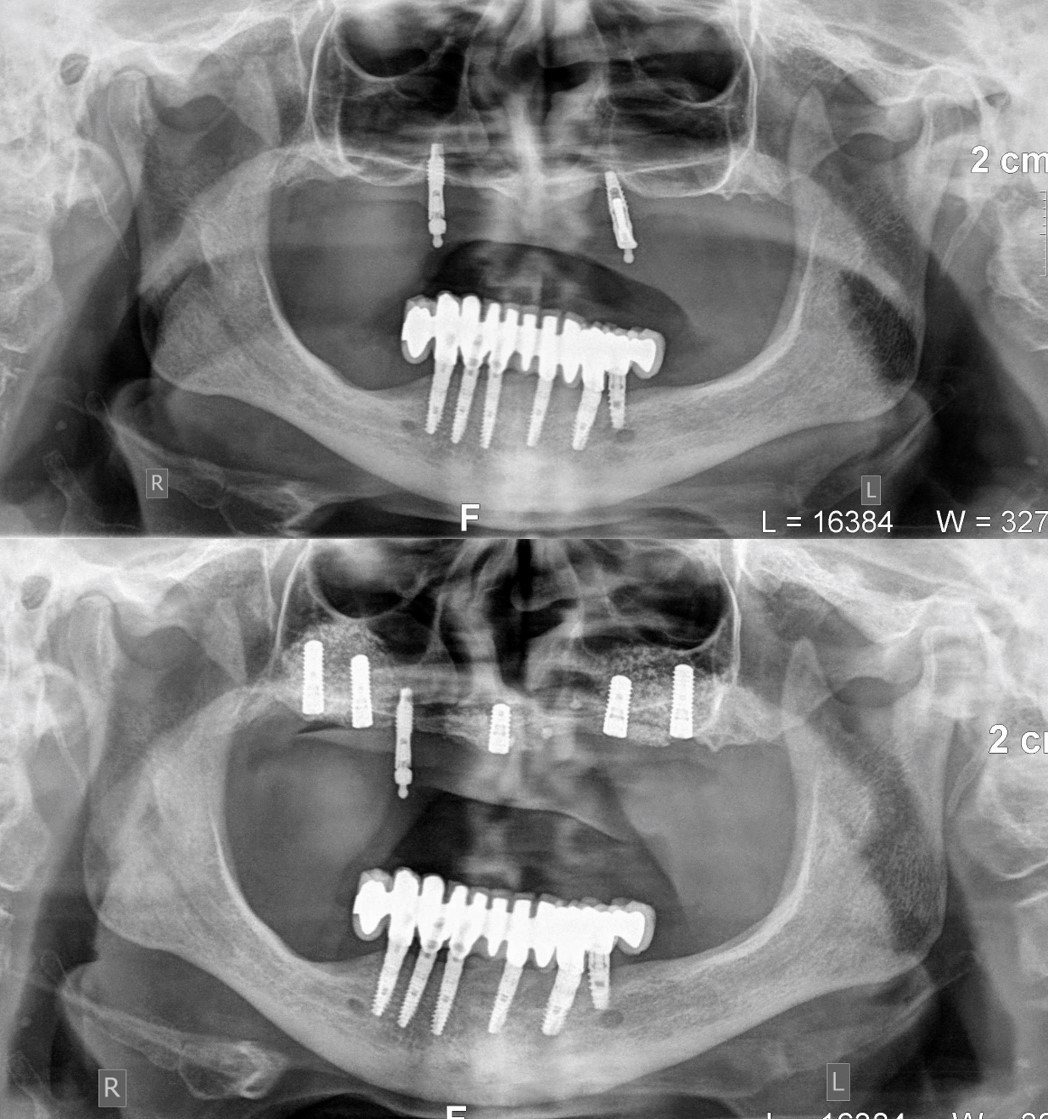

4)       Σε εκτεταμένα ελλείμματα της άνω και της κάτω γνάθου η αποκατάσταση κατά πάχος και καθ’ ύψος της ατροφικής γνάθου μπορεί να γίνει με τη βοήθεια πλέγματος τιτανίου (titanium mesh 3D augmentation), εντός του οποίου στοιβάζεται κοκκώδες αυτομόσχευμα από ενδοστοματική ή εξωστοματική δότρια θέση. Το πλέγμα ακινητοποιείται σταθερά με micro βίδες οστεοσύνθεσης και η επανείσοδος για την αφαίρεση αυτών των υλικών και την τοποθέτηση οδοντικών εμφυτευμάτων προγραμματίζεται να γίνει μετά από 4 ως 6 μήνες (Εικόνα 16).